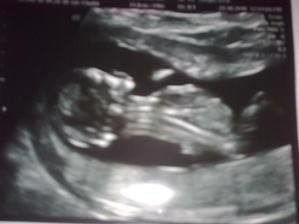

Naša lásočka 13+0tt...už teraz ju milujeme!)))